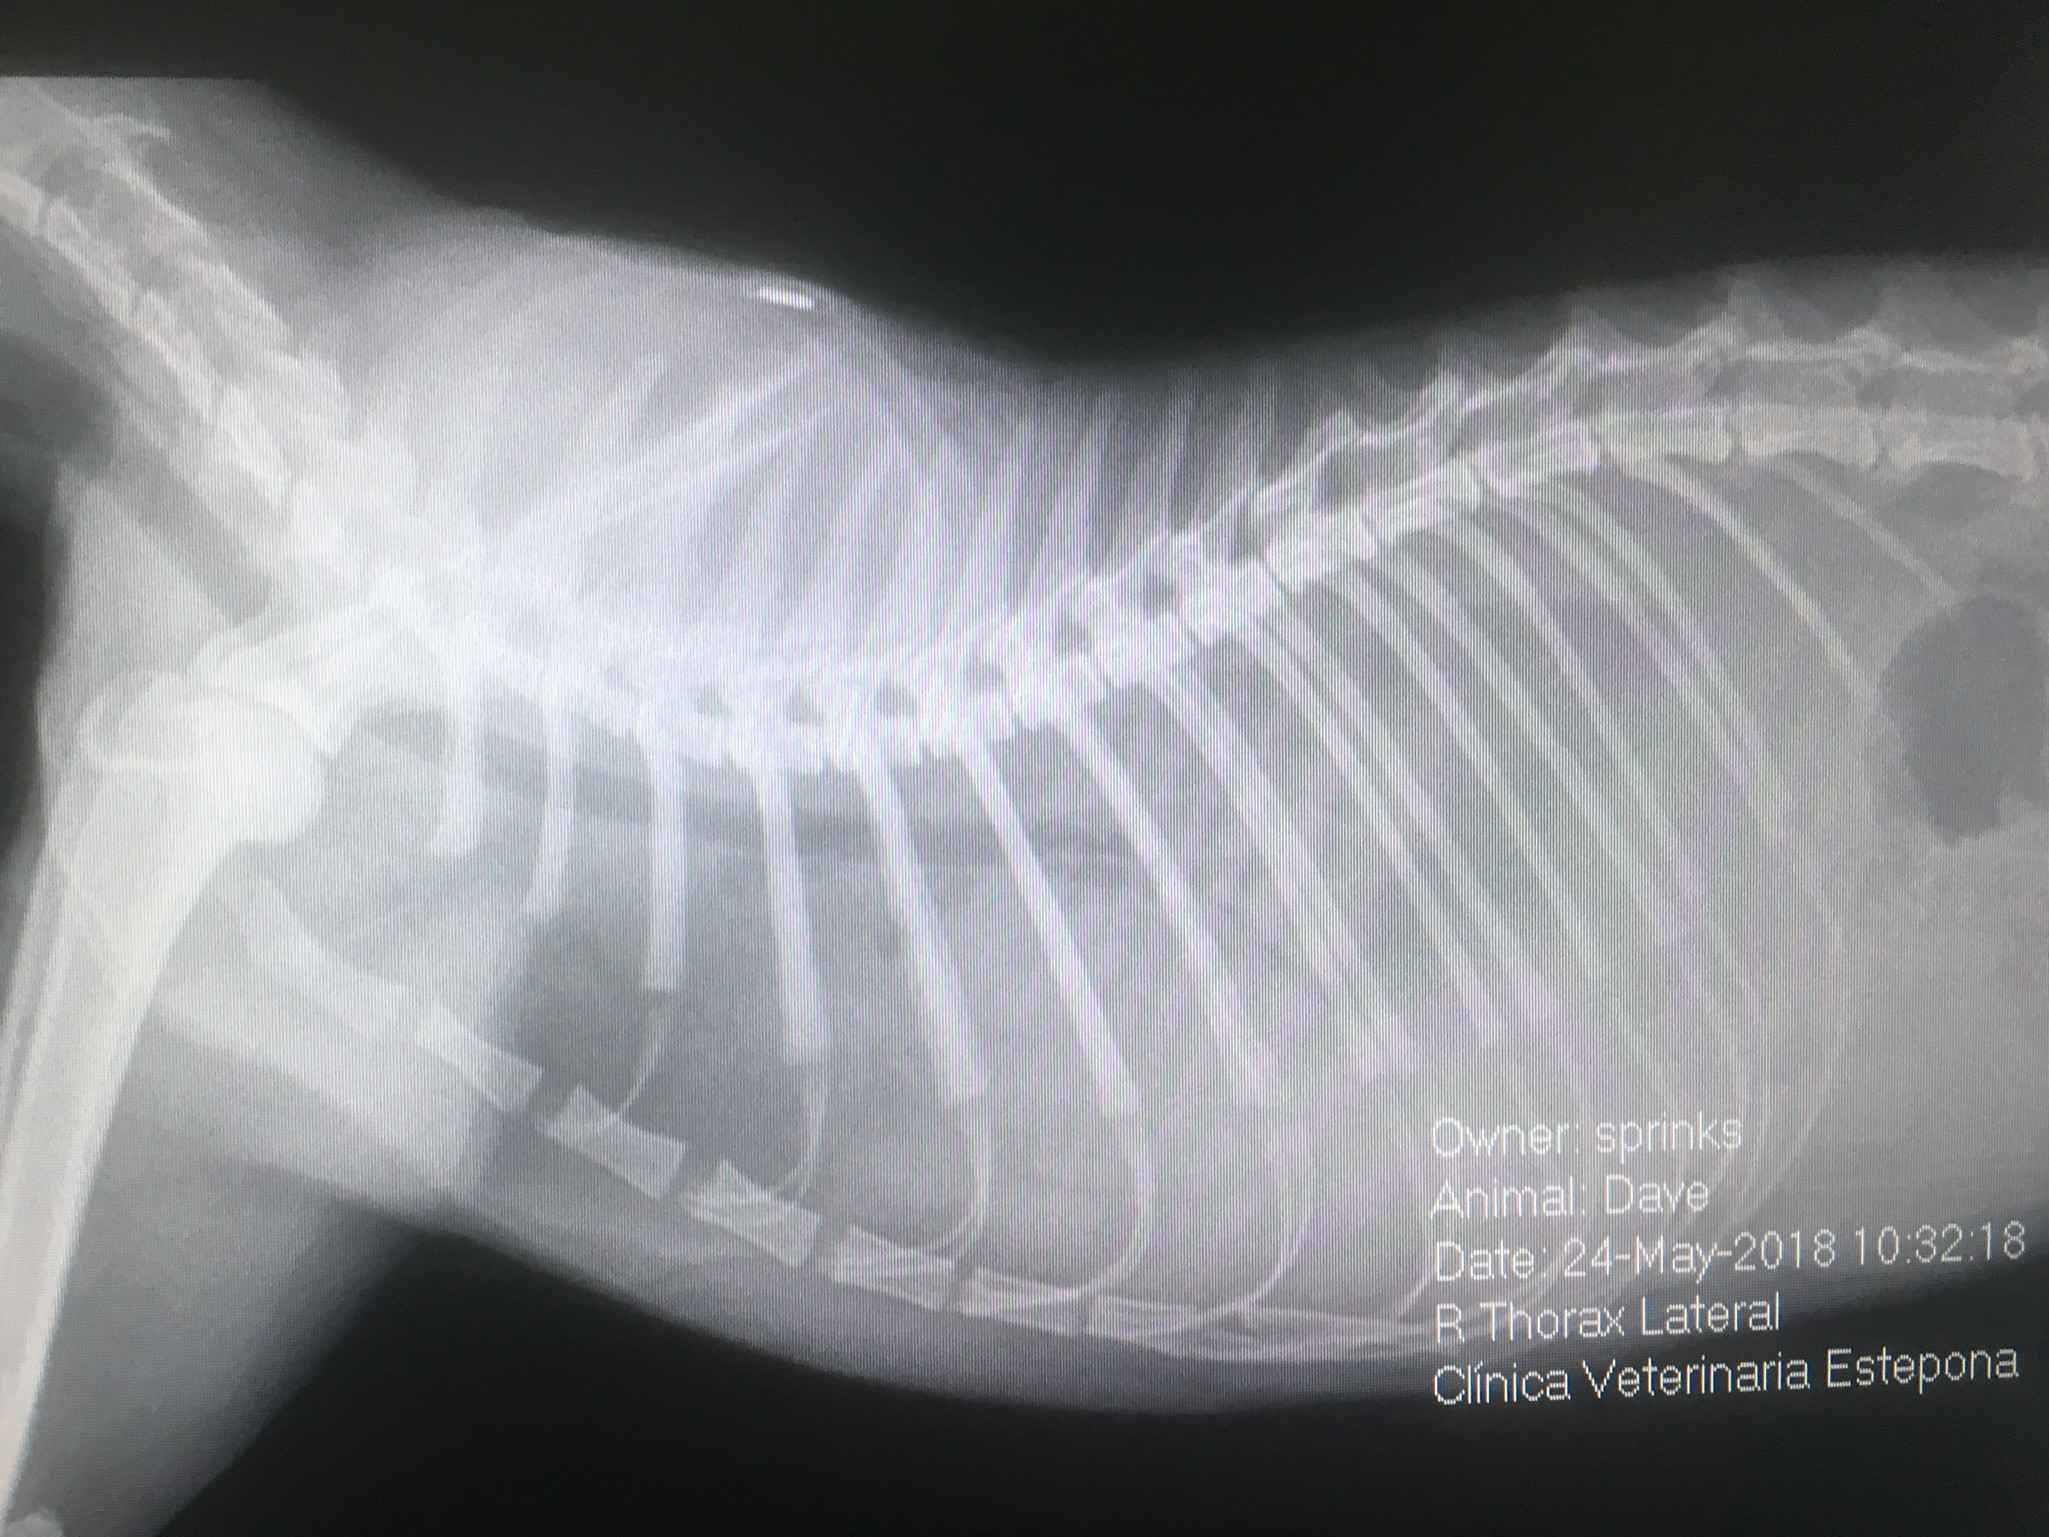

Andererseits ist die Radiologie sehr nützlich für die Diagnose von Knochen-, Bauch- und Brustpathologien. In der Tierklinik Estepona setzen wir nicht nur auf die klassische Radiologie, sondern auch auf die kontrastreiche Radiologie, so dass spezialisierte radiographische Studien wie z.B.

Myelographie (zur Diagnose von Rückenmarkserkrankungen), Urographie und Zystographie mit positivem oder doppeltem Kontrast (zur Diagnose von Nieren- und Harnwegsproblemen) sowie Verdauungskontraststudien (bei Magen-Darm-Problemen) durchgeführt werden können.